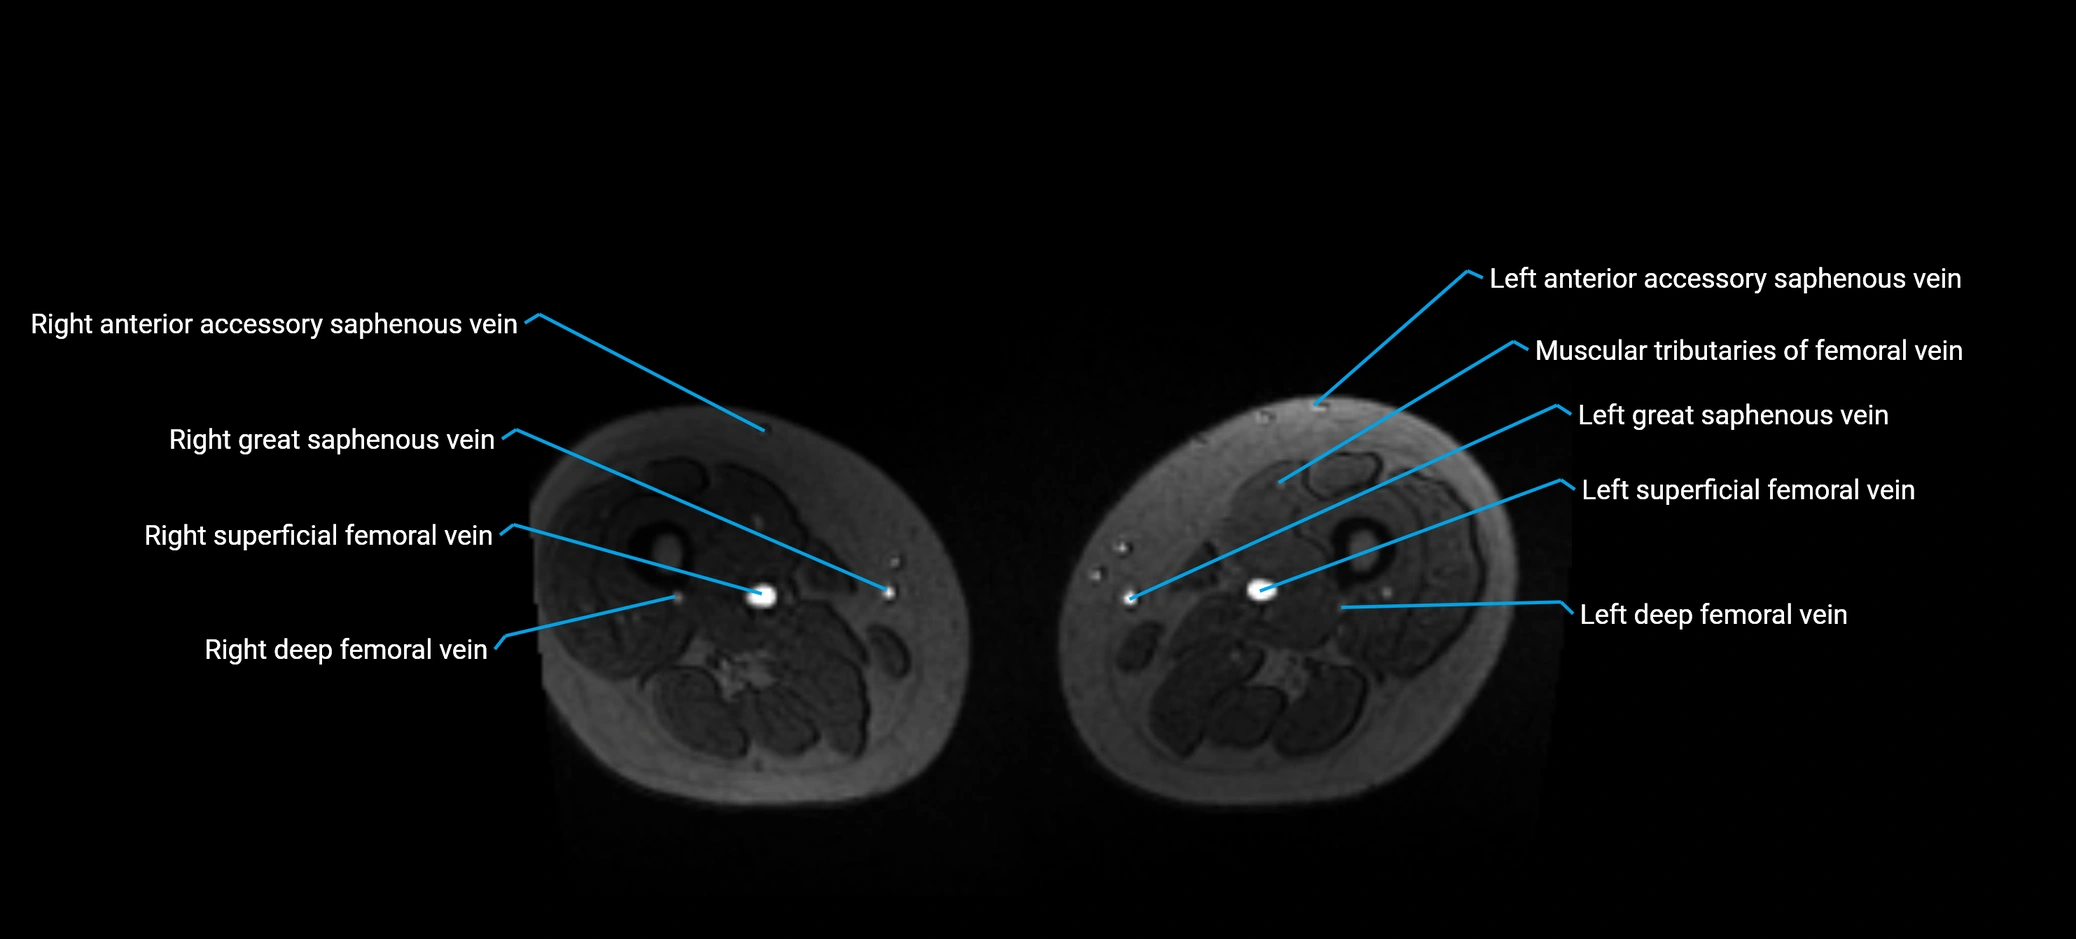

image